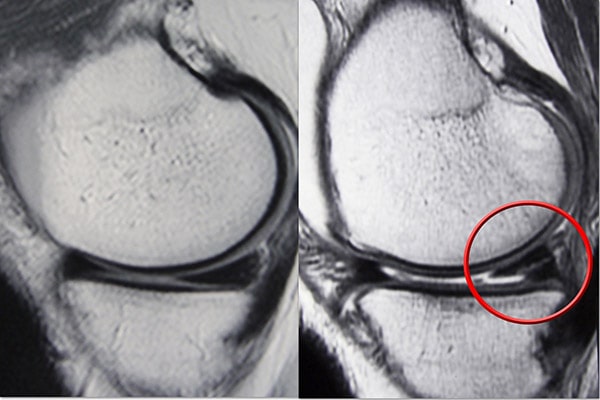

成像測試

由于其他膝蓋受傷也會引起類似的癥狀,您的醫(yī)生可能會要求進(jìn)行影像學(xué)檢查以幫助確認(rèn)診斷。

X光片。 X射線提供致密結(jié)構(gòu)的圖像,例如骨骼。雖然 X 光片不會顯示半月板撕裂,但您的醫(yī)生可能會要求檢查膝關(guān)節(jié)疼痛的其他原因,例如骨關(guān)節(jié)炎。

磁共振成像 (MRI) 掃描。 MRI 掃描可評估膝關(guān)節(jié)的軟組織,包括半月板、軟骨、肌腱和韌帶。